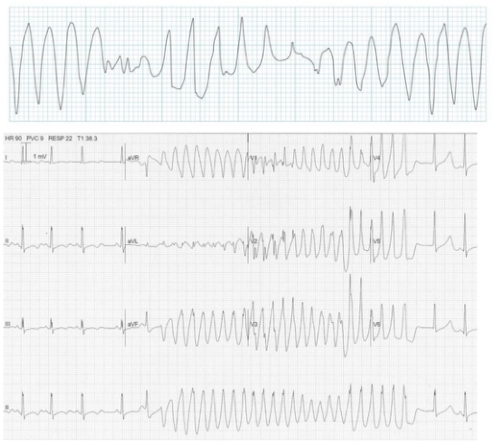

Irregular:

The most common causes of Irregular Broad complex tachycardia are:

- Atrial fibrillation with bundle branch block

- Polymorphic ventricular tachycardia (Torsades de Pointes)

Polymorphic ventricular tachycardia with prolonged QT interval (Torsades de pointes)

Continuously changing amplitude

Rapid, irregular QRS complexes twisting around baseline

Associated with prolonged QT syndromes, electrolyte imbalance (hypomagnesaemia/hypokalaemia).

Often transient and intermittent